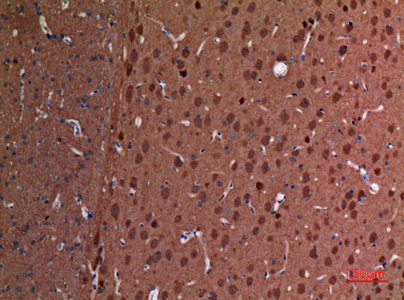

WB,IHC-P,IF-P,IF-F,ICC/IF,ELISA

WB 1:500-1:2000, IHC-P 1:100-300, ELISA 1:20000, IF-P/IF-F/ICC/IF 1:50-200